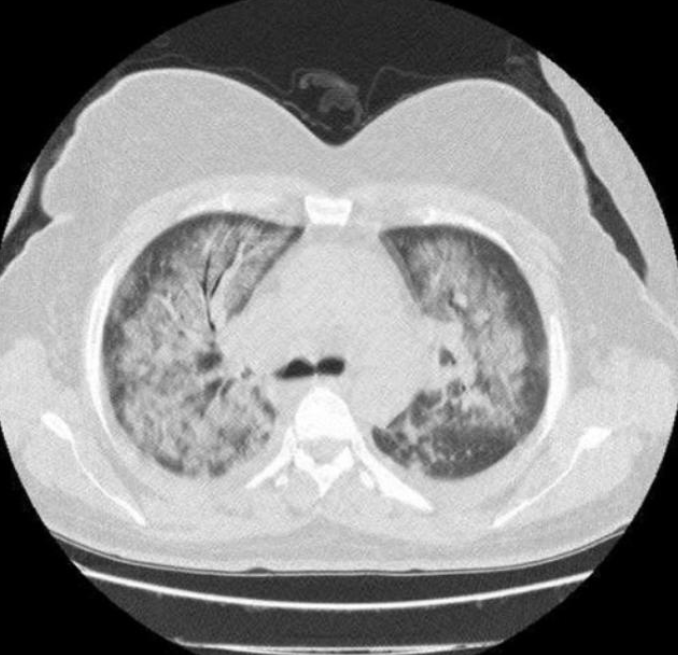

Chest CT에서는 보통 다음과 같은 패턴이 보인다:

- diffuse ground glass opacity

- dependent consolidation

- patchy infiltration

ARDS의 특징적인 영상 소견은

폐의 중력 의존 부위에 더 심한 consolidation이 나타나는 것이다.

이는 폐부종과 폐포 허탈이 중력에 따라 분포하기 때문이다.